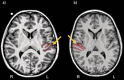

Among the various asymmetrical structures of the human brain, the planum temporale, an anatomical region associated with a variety of auditory and language-related processes, has received particular attention. While its surface area has been shown to be greater in the left hemisphere compared to the right in about two-thirds of the general population, altered patterns of asymmetry were revealed by post mortem analyses in individuals with developmental dyslexia. These findings have been inconsistently replicated in magnetic resonance imaging studies of this disorder. In this report, we attempt to resolve past inconsistencies by analyzing the T1-weighted MR images of 81 children (mean age: 11 years, sd: 17 months), including 46 control (25 boys) and 35 dyslexic children (20 boys). We manually outlined Heschl's gyri, the planum temporale and the posterior rami of the Sylvian fissure on participants' brain images, using the same anatomical criteria as in post mortem studies. Results revealed an altered pattern of asymmetry of the planum temporale surface area in dyslexic boys only, with a greater proportion of rightward asymmetrical cases among dyslexic boys compared to control boys. Additionally, analyses of cortical thickness showed no asymmetry differences between groups for any of the regions of interest. Finally, a greater number of Heschl's gyrus full duplications emerged for the right hemisphere of dyslexic boys compared to controls. The present findings confirm and extend early post mortem observations. They also stress the importance of taking gender into account in studies of developmental dyslexia.